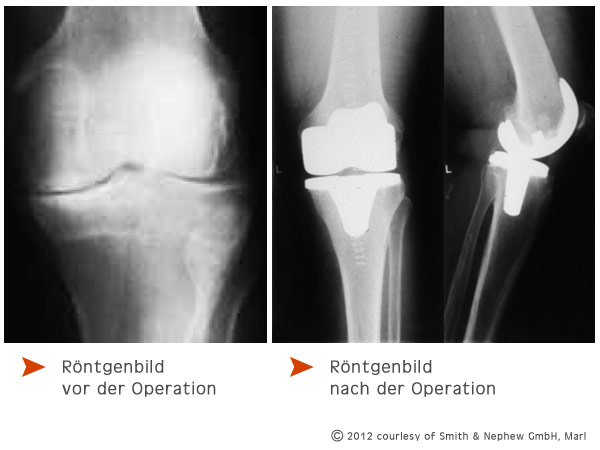

Wirklich wichtig ist für Sie, dass der Arzt die optimale Prothese für Ihre Bedürfnisse ausgewählt hat. Dank seiner langen Erfahrung wird der Arzt Ihre Gelenkgeometrie so natürlich wie möglich wieder herstellen. Fehlstellungen werden möglichst beseitigt, die Prothesen-Komponenten optimal ausgerichtet, um den noch vorhandenen Bändern beim Beugen und Strecken die richtige Spannung zu geben.

Nach dem Eröffnen des Gelenks bereitet Ihr Operateur die Ober- und Unterschenkelknochen für die Befestigung der Implantate vor und beginnt mit der Implantation der Prothesen.